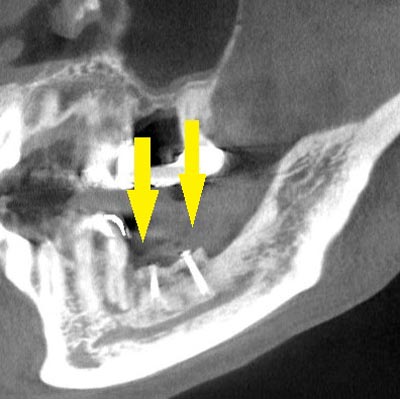

インプラントを埋入するために、骨を増やす方法はいくつかありましたが、この場合、患者様ご自身の骨をブロック状で移植するのが最も適していると判断し、自家骨移植術を行ないました。患者様ご自身の下顎前歯の下方から骨を採取して、骨がなかった部位に移植し、スクリューで固定したCT画像です。黄色矢印部分が、2つの骨片を移植して、固定したところです。

インプラントを埋入するために、骨を増やす方法はいくつかありましたが、この場合、患者様ご自身の骨をブロック状で移植するのが最も適していると判断し、自家骨移植術を行ないました。患者様ご自身の下顎前歯の下方から骨を採取して、骨がなかった部位に移植し、スクリューで固定したCT画像です。黄色矢印部分が、2つの骨片を移植して、固定したところです。